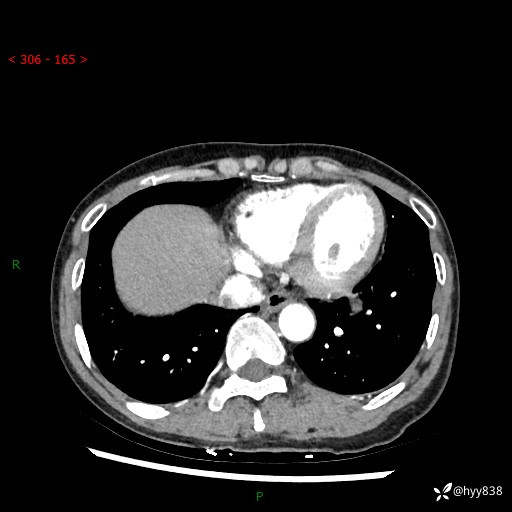

【检查】:胸部CT平扫+增强

各期CT值:40hu 57hu 49hu